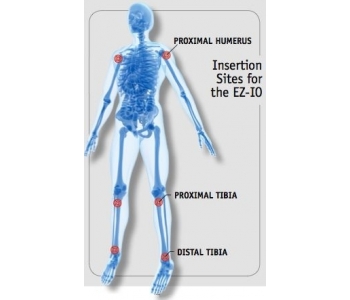

Arrow® EZ-IO® uses the intraosseous space of the humerus, tibia, and distal femur (pediatrics) as a large, non-collapsible vein. It is particularly beneficial for patients who require multiple IV sticks to obtain vascular access for medication.